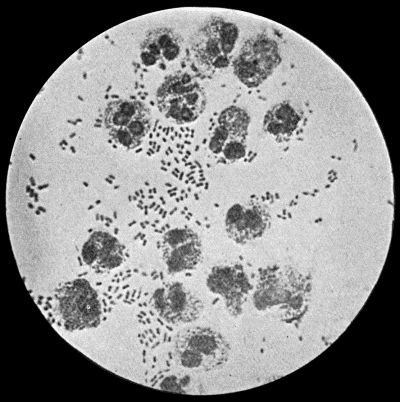

Fig. 4.—Bacillus coli communis in Urine, from a case of Cystitis. × 1000 diam. Leishman's stain.

Bacillus Coli Communis.—This organism, which is a normal inhabitant of the intestinal tract, shows a great tendency to invade any organ or tissue whose vitality is lowered. It is causatively associated with such conditions as peritonitis and peritoneal suppuration resulting from strangulated hernia, appendicitis, or perforation in any part of the alimentary canal. In cystitis, pyelitis, abscess of the kidney, suppuration in the bile-ducts or liver, and in many other abdominal conditions, it plays a most important part. The discharge from wounds infected by this organism has usually a fœtid, or even a fæcal odour, and often contains gases resulting from putrefaction.

It is a small rod-shaped organism with short flagellæ, which render it motile (Fig. 4). It closely resembles the typhoid bacillus, but is distinguished from it by its behaviour in artificial culture media.